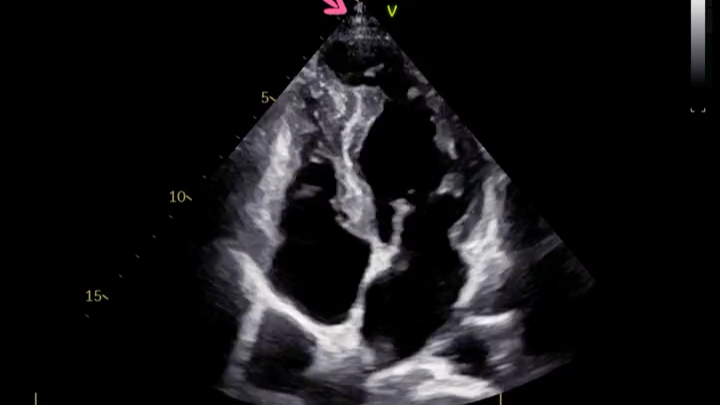

室壁瘤超声表现及鉴别

图片尺寸750x620